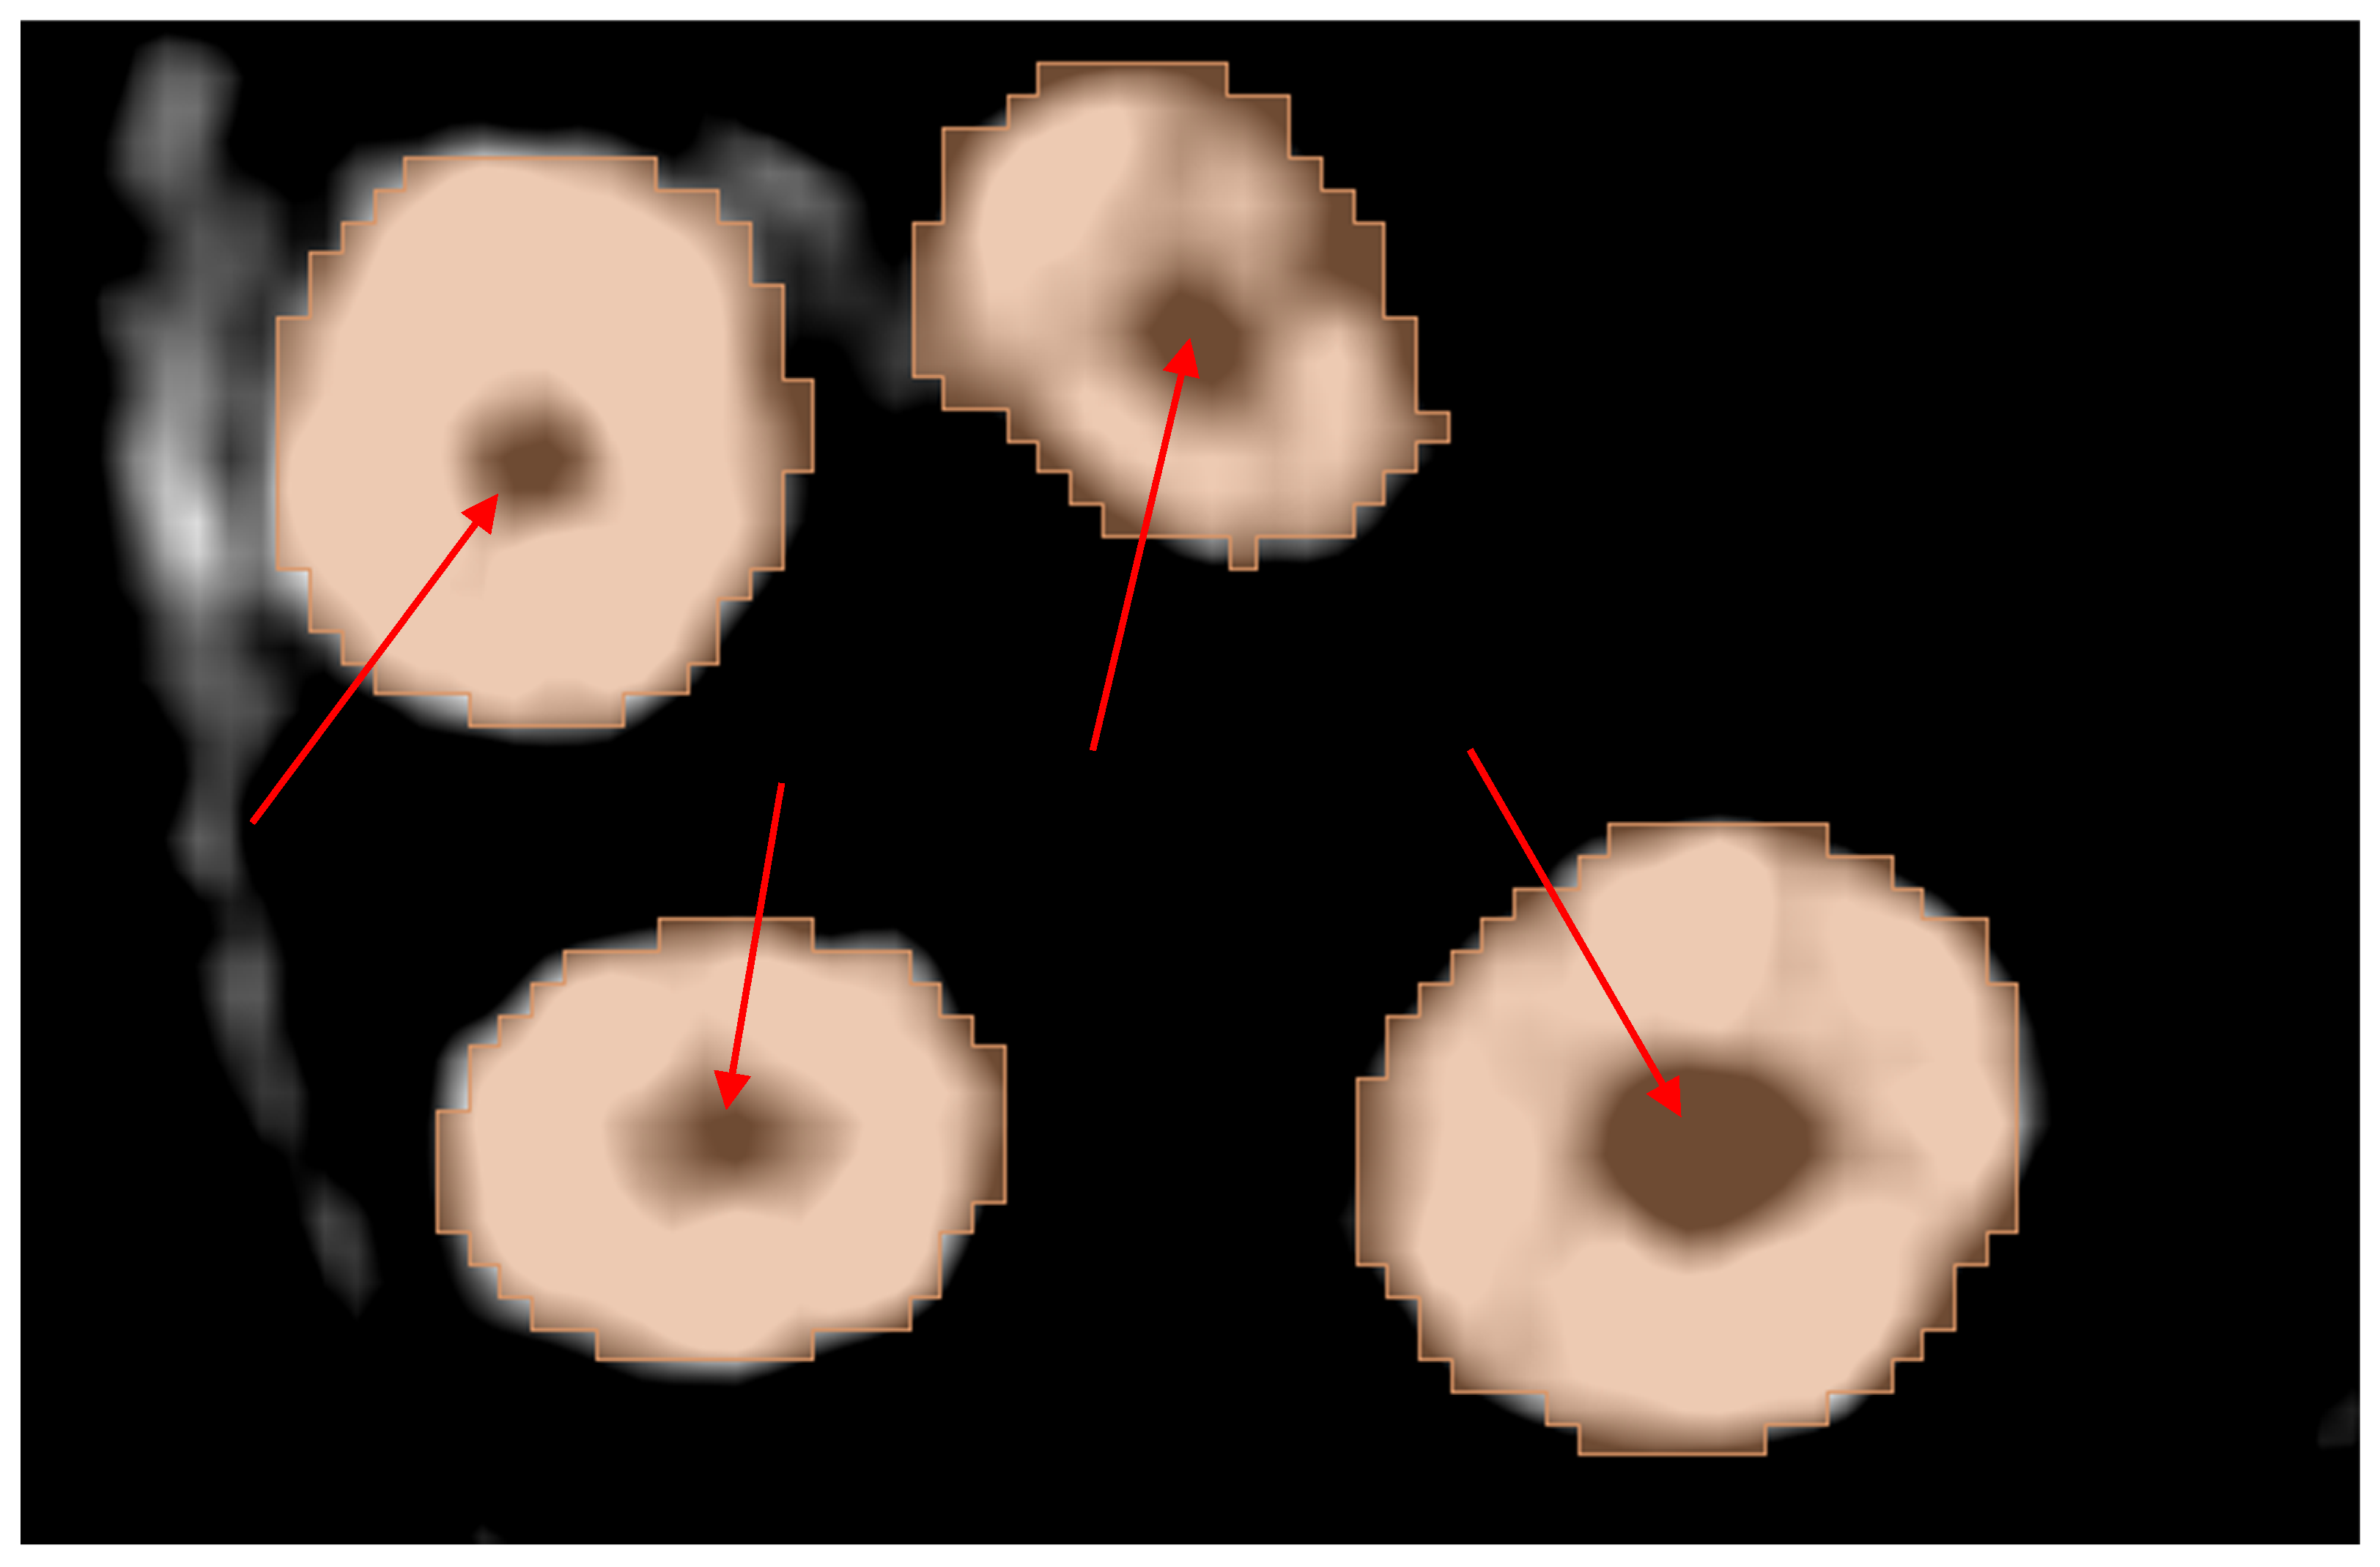

Although visually, the results looked decent in most cases, the statistical testing showed statistical differences in all comparisons made from the manual segmentation groups. Moreover, upon closer inspection, root canal recognition was not of an acceptable level from the point of view of an endodontics-oriented application. Figure 26 shows the four roots in the molar of Dataset 3: mesiobuccal, distobuccal, mesiopalatal, and distopalatal roots. In this figure, the histogram is aggressively modified to better visualize the automated model’s mistake in mislabeling the hollow root canals as part of the solid dentin of the tooth. Having to manually correct this error would be a tedious process and would take away the main benefits of this method, which are autonomy and time savings; at this point, the extension becomes another semi-automated method and not a fully automated one as regarded. The model also failed to account for the orthodontic brackets and wire when segmenting the upper and lower teeth, which raises concerns about other patient-specific datasets and the model’s applicability for such cases.

Figure 26.

The limitation of the automated method in recognizing the root canals visualized by the red arrows.